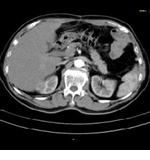

これは、単純に輪切りにした画像です。

その輪切りにした画像を重ね合わせて、上からみた画像はこのようになります。